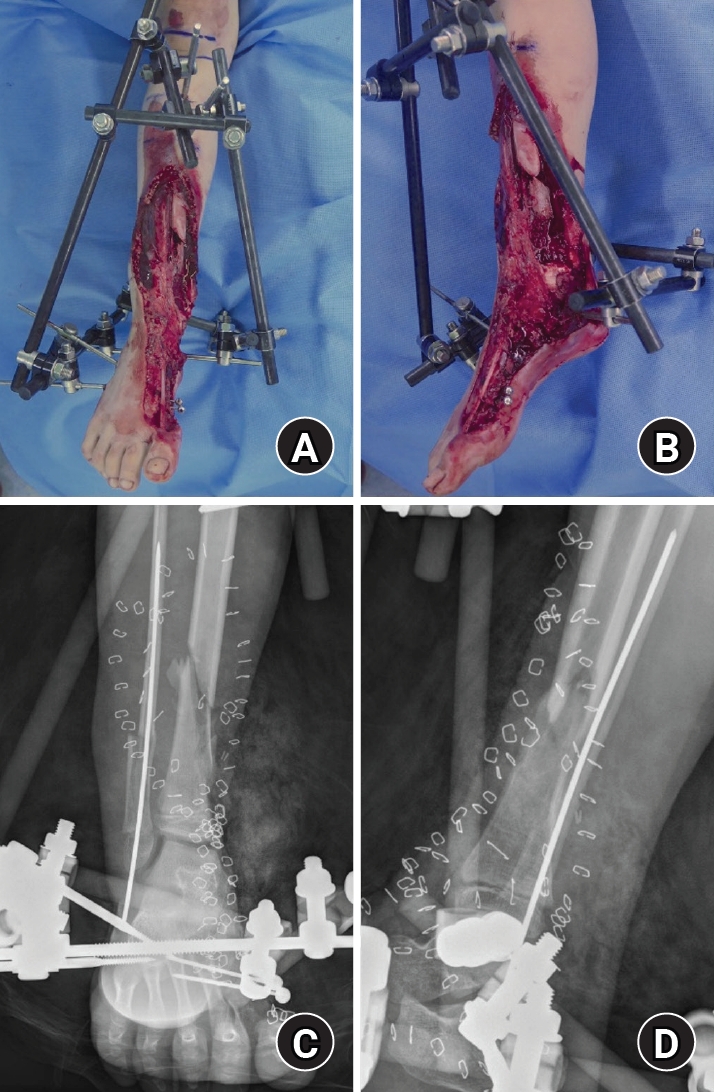

An 8-year-old girl presented after a traffic accident with a severe crush and degloving injury of the medial right ankle and foot, a distal tibiofibular fracture, and medial midfoot bone defects. After staged irrigation and debridement with temporary external fixation, definitive reconstruction was performed on August 6, 2016. The medial malleolar defect (2.5×2.0 cm) was reconstructed using a contoured autologous iliac crest bone graft secured with internal fixation, and medial stability was augmented using harvested gluteal fascia as a deltoid ligament substitute fixed with suture anchors. A bone-cement spacer was placed adjacent to the injured physis to mitigate physeal bridging, and the extensive soft-tissue defect was covered with a free anterolateral thigh flap and skin graft. During follow-up, progressive varus deformity and contracture were managed with corrective osteotomy and plating, Achilles tendon lengthening, Z-plasty, and Ilizarov fixation. At the final follow-up (March 6, 2025), the limb-length discrepancy was 5 mm, active ankle dorsiflexion was 0° (passive dorsiflexion 5°), and the patient was pain-free with full participation in daily activities, including hiking and dancing. This case emphasizes the value of an integrated staged strategy that combines bony reconstruction, medial stabilization, physeal management, and durable soft-tissue coverage during skeletal growth.